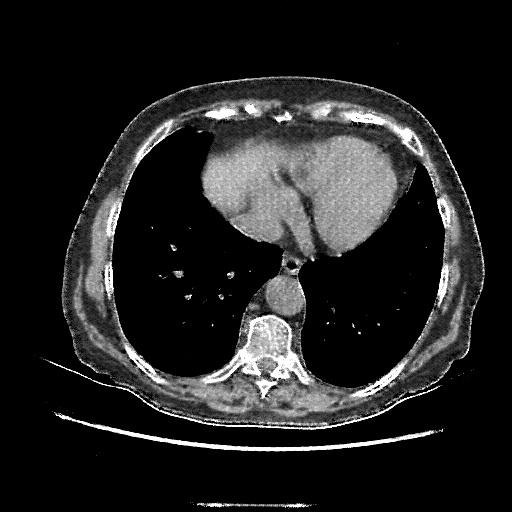

Generated VENOUS CT scan (A→B translation)

Full window (WL 1023.5, WW 4095 β†’ Low βˆ’1024, High +3071)

Mediastinum window (WL 40, WW 400 β†’ Low βˆ’160, High +240)

Targeted Slice 70 - Mediastinum Window Analysis (Generated vs Real Venous)

0.698

Mediastinum SSIM

58.6

Mediastinum RMSE

22.5

Mediastinum MAE